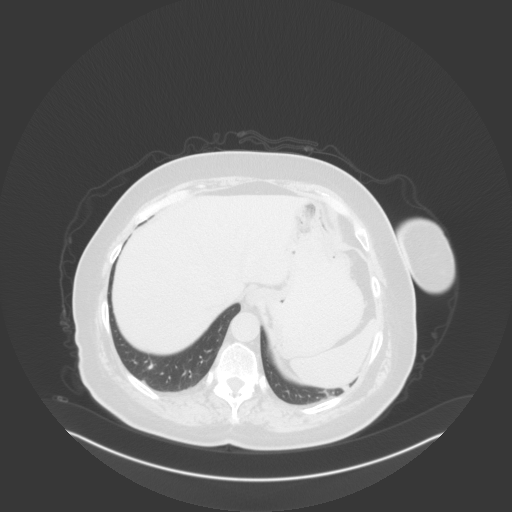

Original VENOUS CT scan

No window - Raw intensity values

Lung window (WL -600, WW 1500 β†’ Low βˆ’1350, High +150)